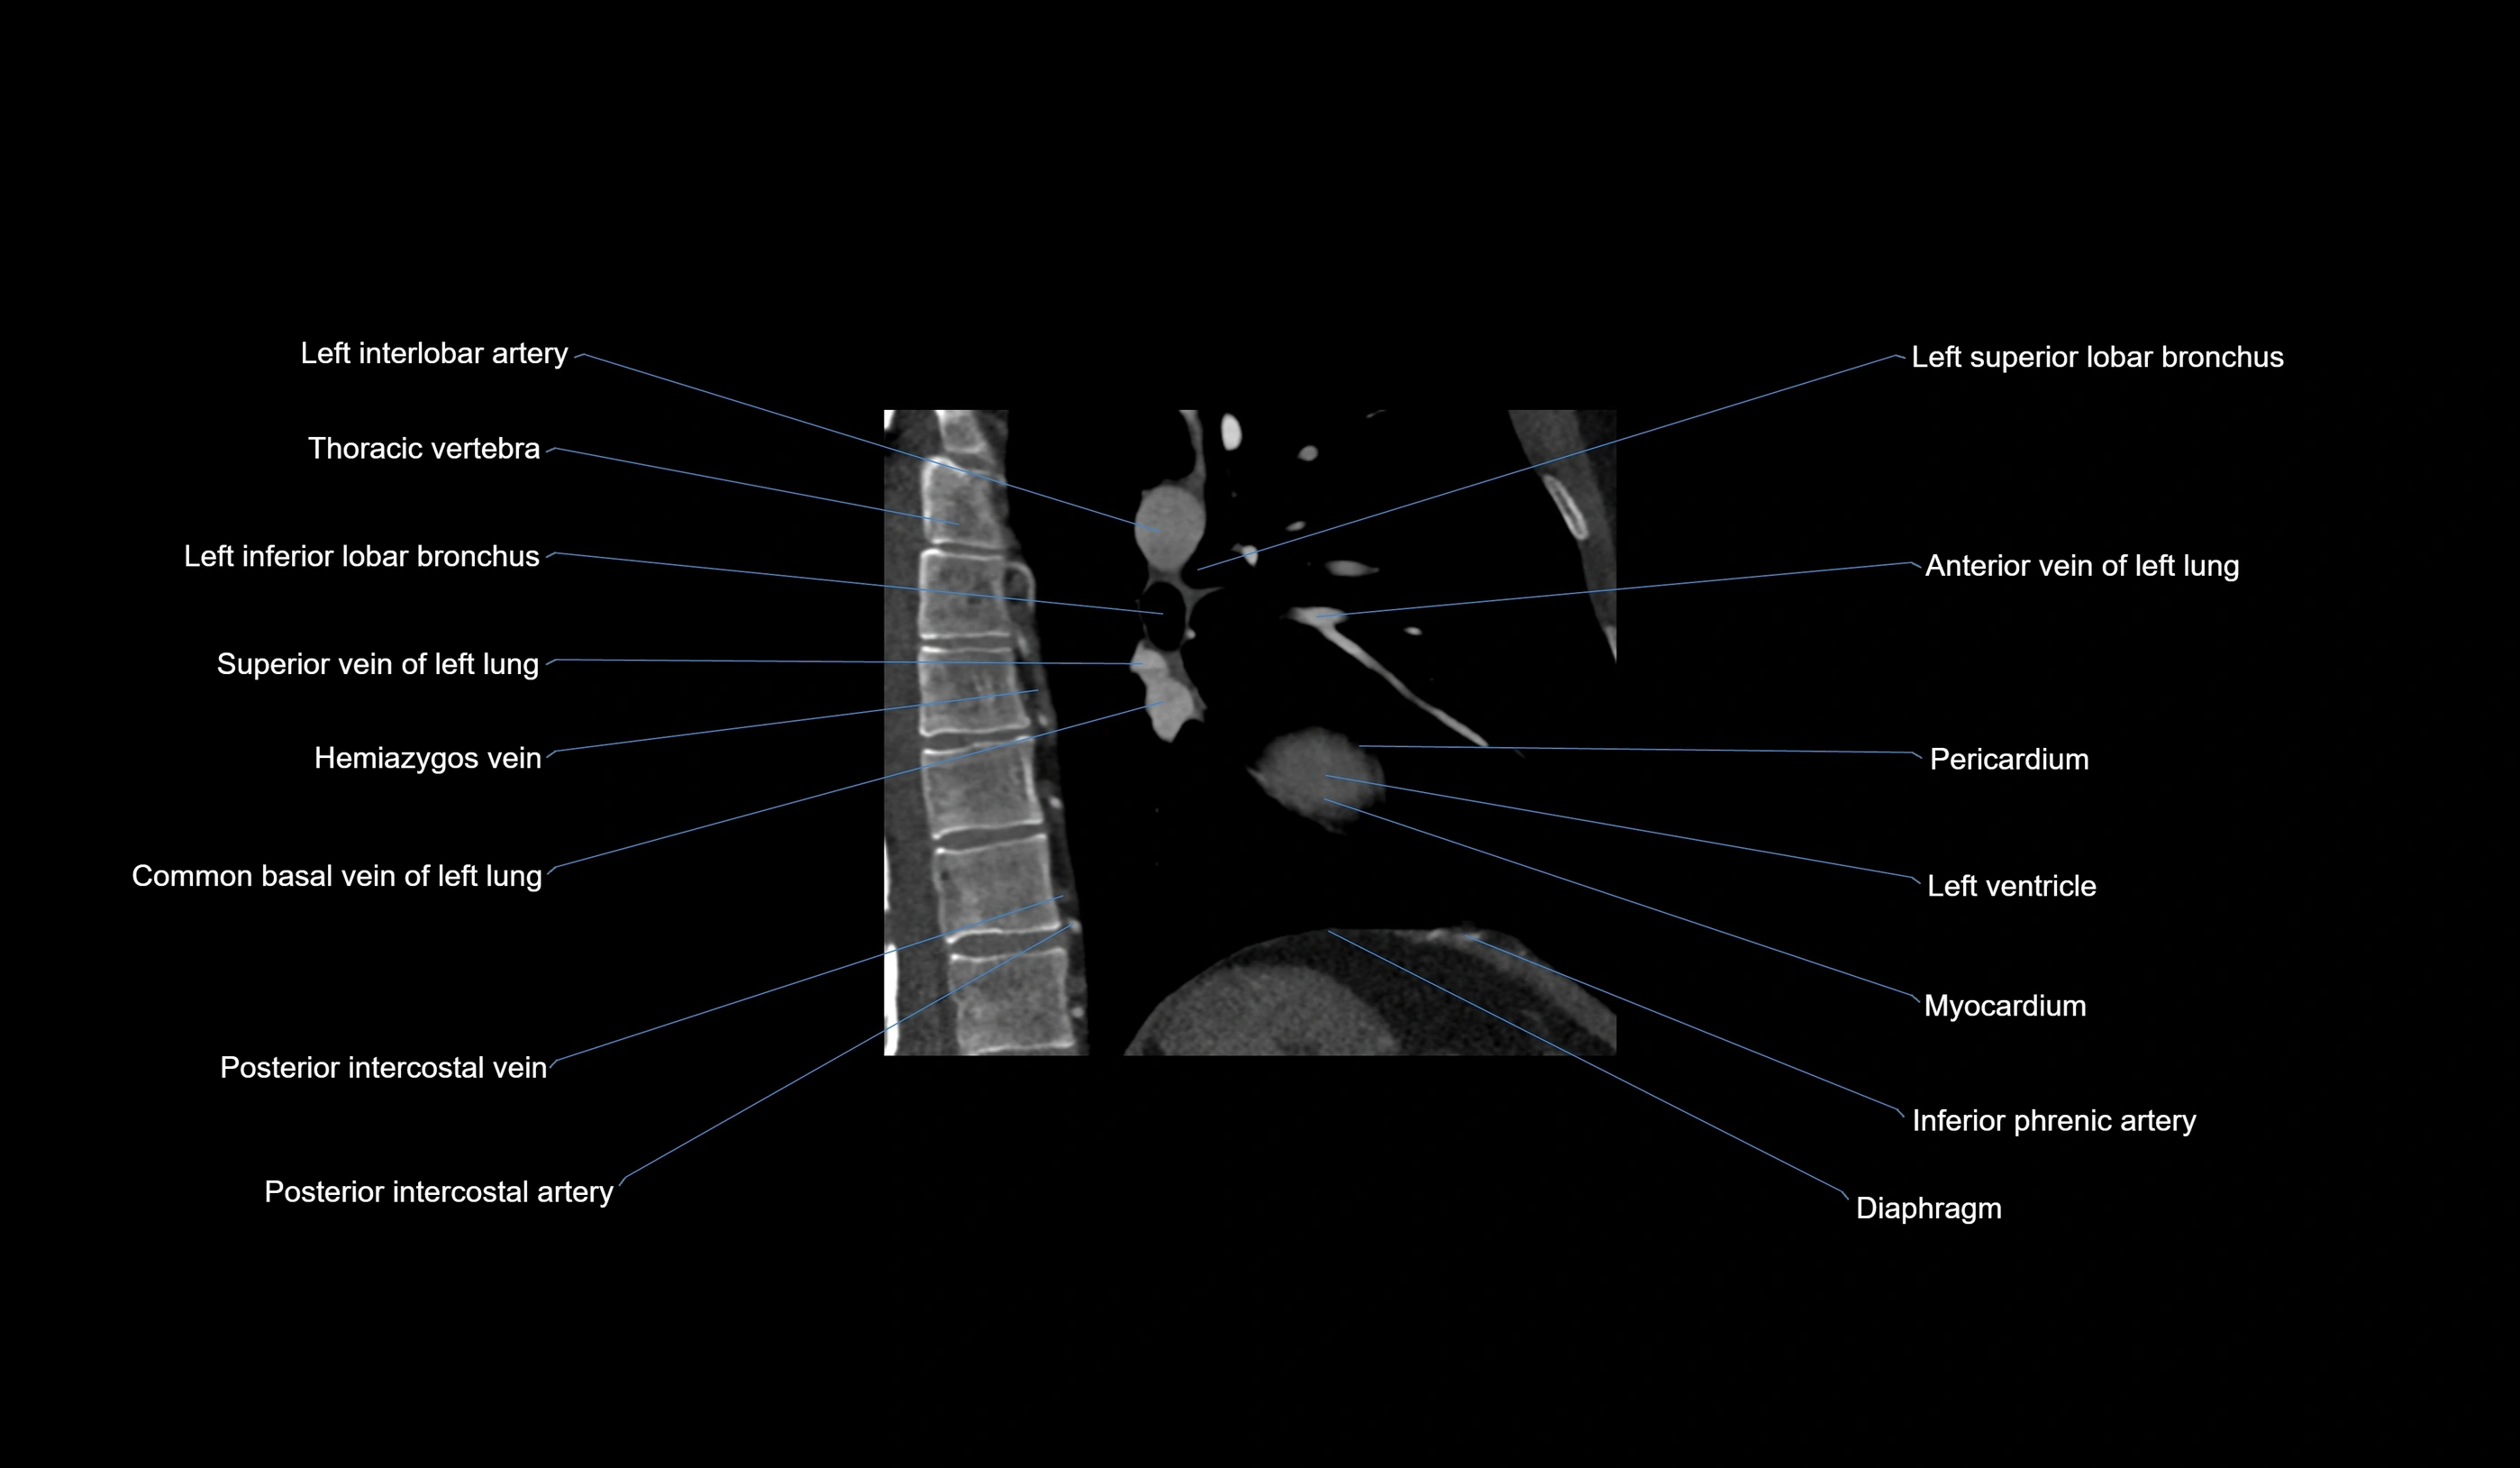

- Acute marginal artery (AM)

CT Appearance

CT Coronary Angiography (CCTA):

-

Best non-invasive modality for acute marginal artery visualization

Shows origin, course along the acute margin, and right ventricular branches

Detects stenosis, occlusion, calcified and non-calcified plaques, aneurysm, or anomalous course

Multiplanar reformats and 3D reconstructions help in pre-PCI and surgical planning

Critical for assessing right ventricular infarction risk in RCA disease

MRI image

CT images